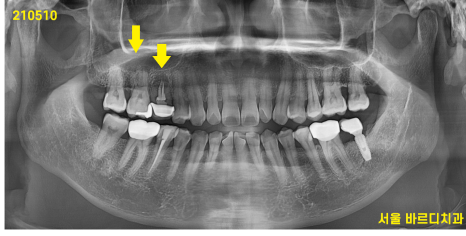

210510~230320

환자분이 예전부터 잇몸이 한번씩 붓는다고 표현해주셨는데요.

21년도 고덕동 치과를 방문하셨을 때 찍은

x-ray에서도 안좋은 부분은 관찰되었습니다.

그때부터 안좋은 시그널을 계속 보냈었는데..

기록을 보니 한번의 스케일링 이후 치과 내원 기록이 없더군요ㅠㅠ

그래서 잇몸 주저앉음 증상을 느끼고 방문하셨을 때에는

손쓸 수 없을 정도로 망가져 내원하셨습니다.